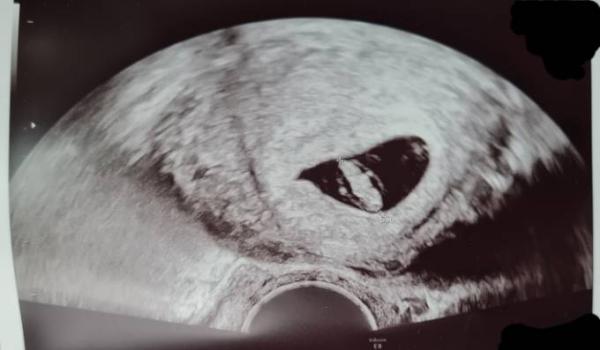

Einen schönen Abend zusammen, wie würdet ihr das Bild (7+2) anhand der Ramzi-Methode beurteilen, Junge oder Mädchen? Ich weiss, das Bild erfüllt wahrscheinlich nicht mal alle Voraussetzungen, aber ist ja auch mehr spaßhaft zu sehen (Das Beschäftigungsverbot bringt einen immer wieder auf interessante Ideen )

Antwort auf Beitrag von Bananenshake

Tut mir leid aber in dieser frühen Zeit entwickeln sich die Geschlechtsorgane noch aus. Du musst leider noch ein paar wochen warten bzw sogar Monate